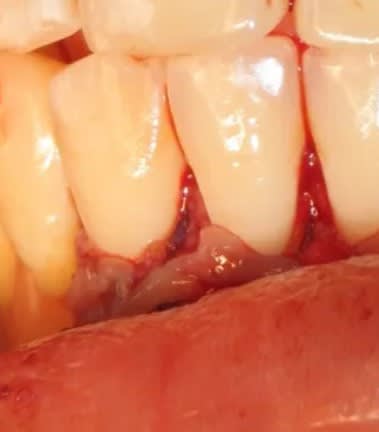

mais serieusement, la c'était vraiment fini ? elle est allée en salle de réveil comme ca ?? :

non, comme ça!

donc elle est bien allee en salle de reveil non suturee... vache...

la sincèrement c est quand meme pas terrible... je veux bien rigoler un peu mais ca c est pas acceptable.